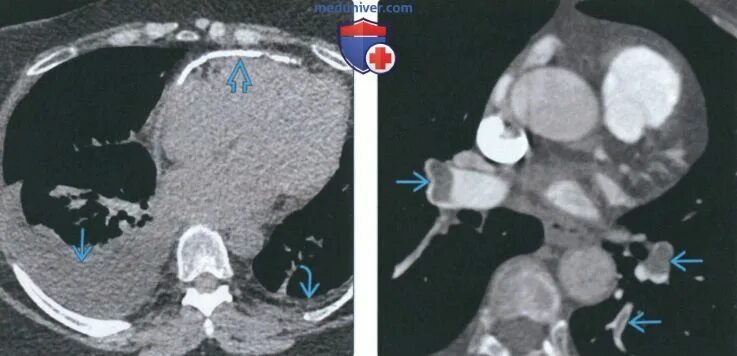

Гипостатические изменения кт